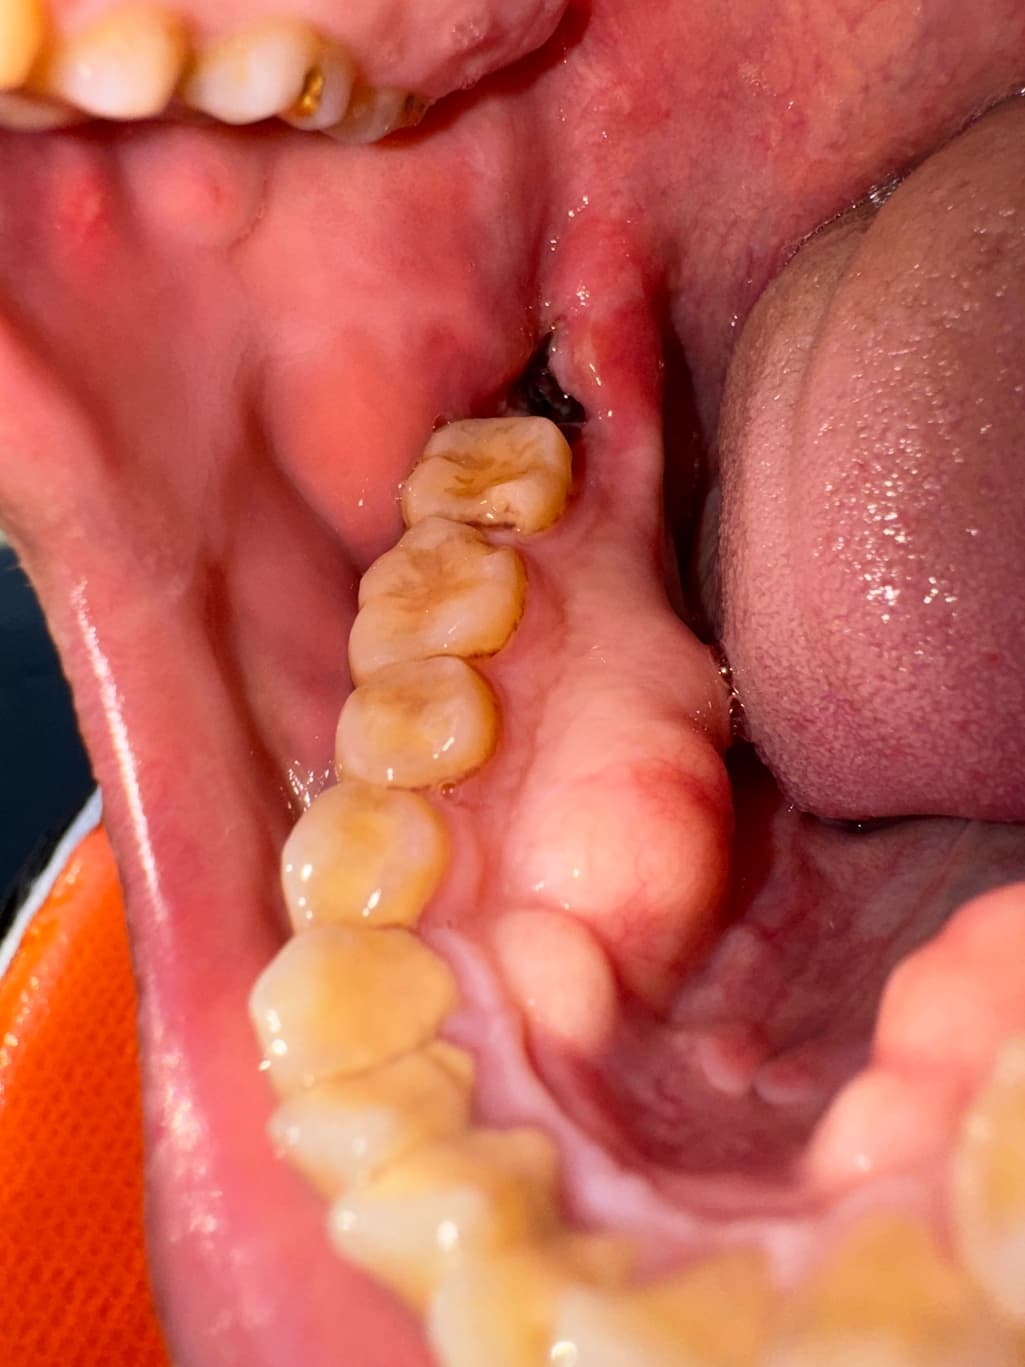

사랑니 발치 후, 이거 제대로 아물고있는게 맞나요

어제 뽑고 하루 지났어요,

제대로 아물고 있는게 맞나요, 혈병 상태도 괜찮은가 궁금하네요, 혹시 제대로 아물고 있는게 맞을까요?

제대로 아물고 있는게 맞나요, 혈병 상태도 괜찮은가 궁금하네요, 혹시 제대로 아물고 있는게 맞을까요? -> 지금으로선 문제 있어보이진 않아요 완전히 아물려면 한달은 있어야 합니다

사진으로 봤을 경우에는 크게 문제가 없이 아물고 있는 것으로 보입니다. 발치한 부위가 잘 아물기 위해서는 자극되지 않는 것이 좋습니다. 대부분의 발치를 한 통증은 3~4일 정도 지나면 없어지게 되며 발치한 부위가 아무는 데는 2주 정도의 시간이 걸리게 됩니다.

사랑니 발치 후 사진상으로는 문제 없이 잘 낫고 있는 것으로 보입니다. 걱정안하셔도 될 듯 합니다.

사진상으로 발치한곳은 잘아물고 잇는거 같으니 자극만 가지 않도록 해주시면될것같습니다.